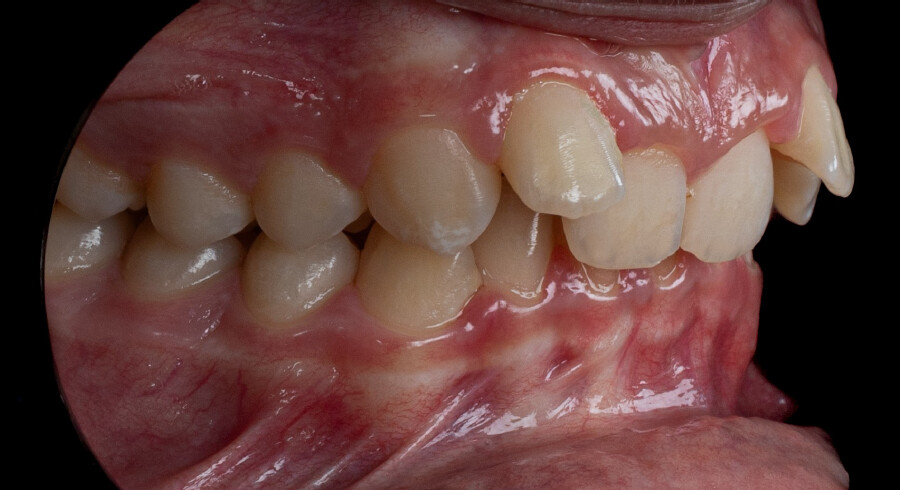

A 13-year-old male patient presented with a deep bite, characterized by near-complete coverage of the mandibular incisors. Clinical evaluation revealed bi-arch crowding, dental rotations, and proclination of the maxillary lateral incisors, contributing to the patient’s esthetic concerns. The facial profile was retrusive, consistent with mandibular retrognathism, and no significant periodontal abnormalities were detected.

The patient presented with a skeletal Class II relationship with bilateral molar and canine Class II and a Class II division 2 dental pattern. The deep bite was associated with anteroinferior crowding and an accentuated Curve of Spee. Facial analysis revealed good symmetry, a slightly increased lower facial third, and a convex profile characterized by mandibular and chin retrusion. Lip competence was mildly reduced, with a decreased nasolabial angle and mentalis hyperactivity, all of which compromised overall facial harmony.